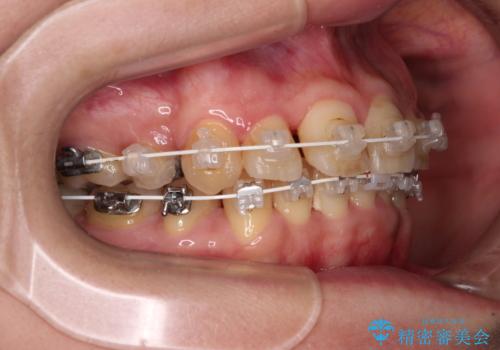

- 海外で抜歯矯正を開始し、治療途中で帰国したため、転院先を探しているとのことで来院された患者様です。

ワイヤーは抜けてしまい、後戻りが始まっている状態でしたが、既存の装置を継続利用して受け入れてくれる医院が見つからないとのことでした。

当院では、張り替える必要のある部位は張り替えることで継続することとし、抜歯スペースを閉じていくように治療を行うこととしました。